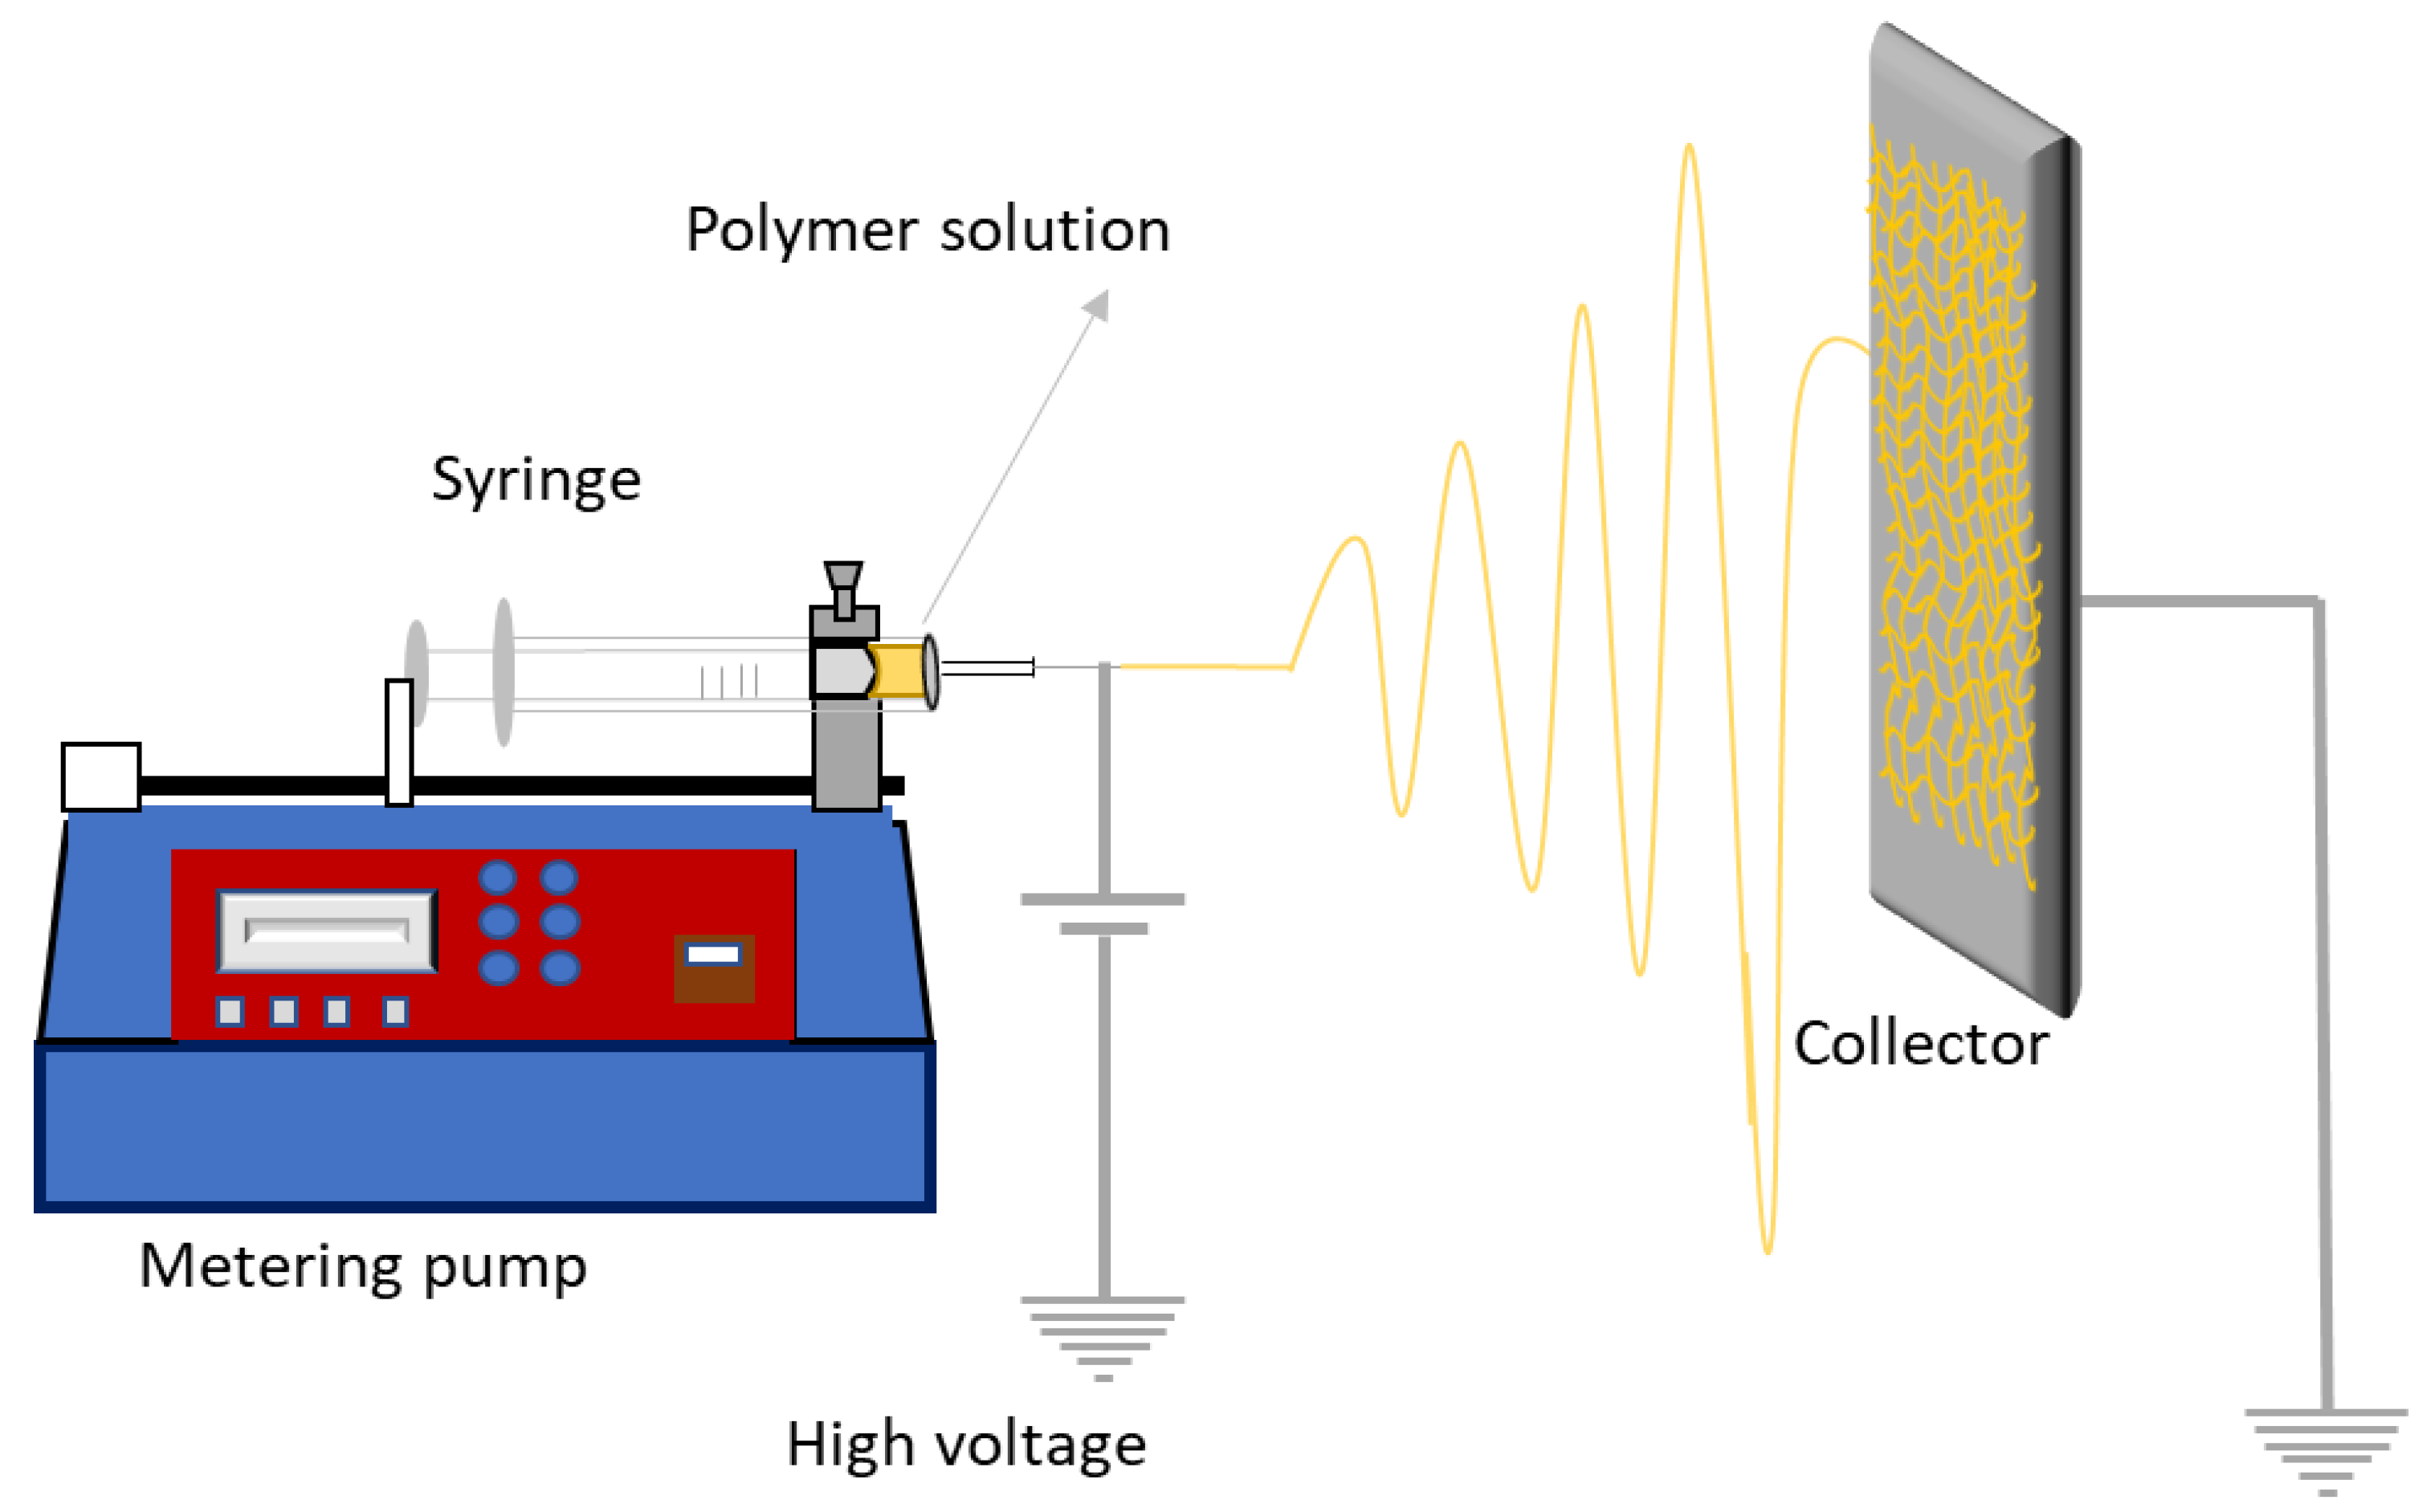

5.2. Electrospinning

- Xue, J.; Wu, T.; Dai, Y.; Xia, Y. Electrospinning and Electrospun Nanofibers: Methods, Materials, and Applications. Chem. Rev. 2019, 119, 5298–5415. [Google Scholar] [CrossRef]

- Haider, A.; Haider, S.; Kang, I.-K. A comprehensive review summarizing the effect of electrospinning parameters and potential applications of nanofibers in biomedical and biotechnology. Arab. J. Chem. 2018, 11, 1165–1188. [Google Scholar] [CrossRef]

- Chinnappan, B.A.; Krishnaswamy, M.; Xu, H.; Hoque, E. Electrospinning of Biomedical Nanofibers/Nanomembranes: Effects of Process Parameters. Polymers 2022, 14, 3719. [Google Scholar] [CrossRef]

- Omer, S.; Forgách, L.; Zelkó, R.; Sebe, I. Scale-up of electrospinning: Market overview of products and devices for pharmaceutical and biomedical purposes. Pharmaceutics 2021, 13, 286. [Google Scholar] [CrossRef]